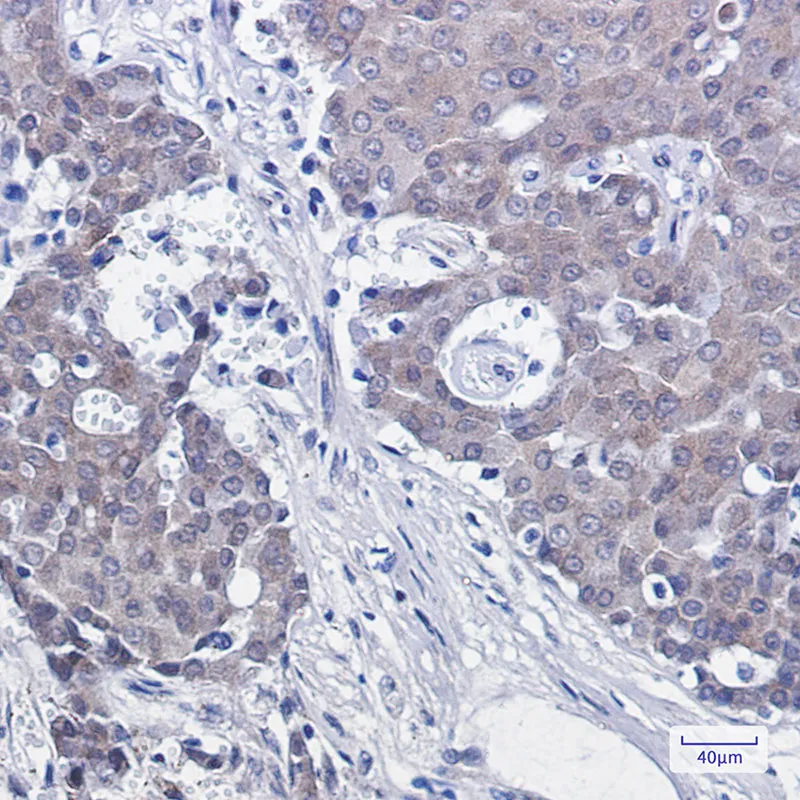

Cytokeratin 19 Rabbit Monoclonal Antibody

Cat: AMRe01888